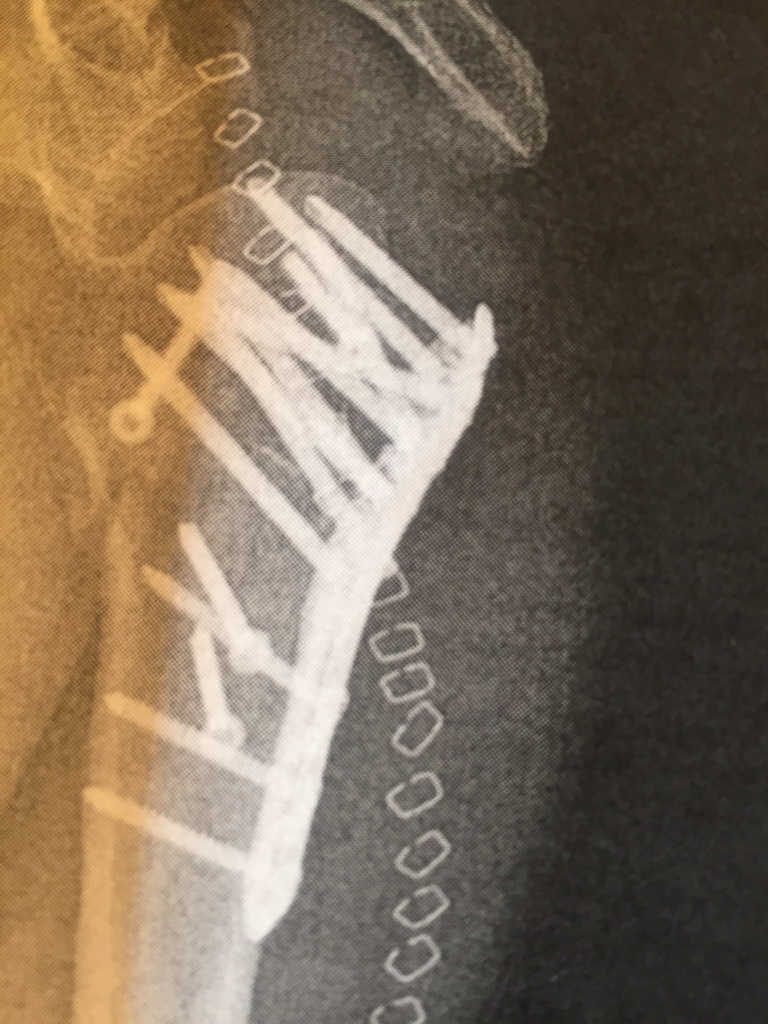

Nach Unfall im Oktober 2014 mit mehreren Brüchen im Fuß und Unterschenkel habe ich im Januar auch "ganz langsam" wieder mit dem Joggen angefangen und bin im Moment bei 4 Trainingseinheiten à 7 Km / Woche.